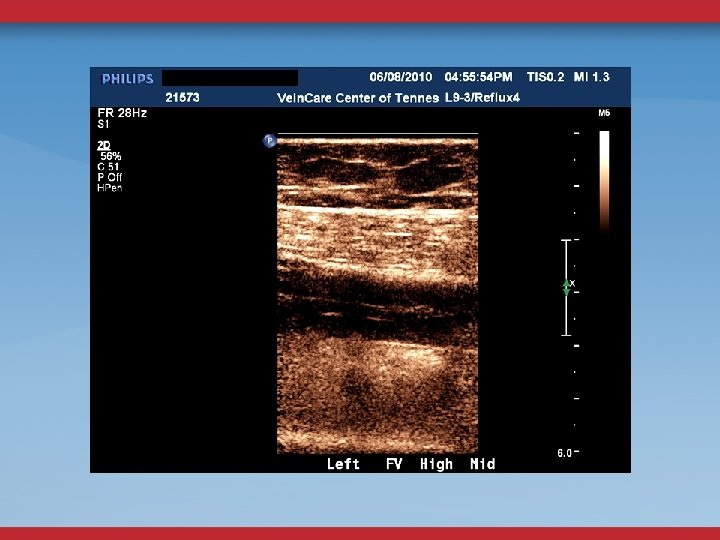

LE VENOUS DUPLEX US REFLUX OBSTRUCTION CFV DOPPLER FLOW CONTINUOUS? ASYMMETRY? FEMORAL VEIN COLLATERALS

ABDOMINAL/PELVIC DUPLEX FLOW AND ANATOMY STENOSIS MINOR DIAMETER REDUCTION ELEVATED PEAK VENOUS VELOCITY RATIO >2. 5 FLOW REVERSAL GONADAL, ASCENDING LUMBAR, PELVIC VARICOSITIES